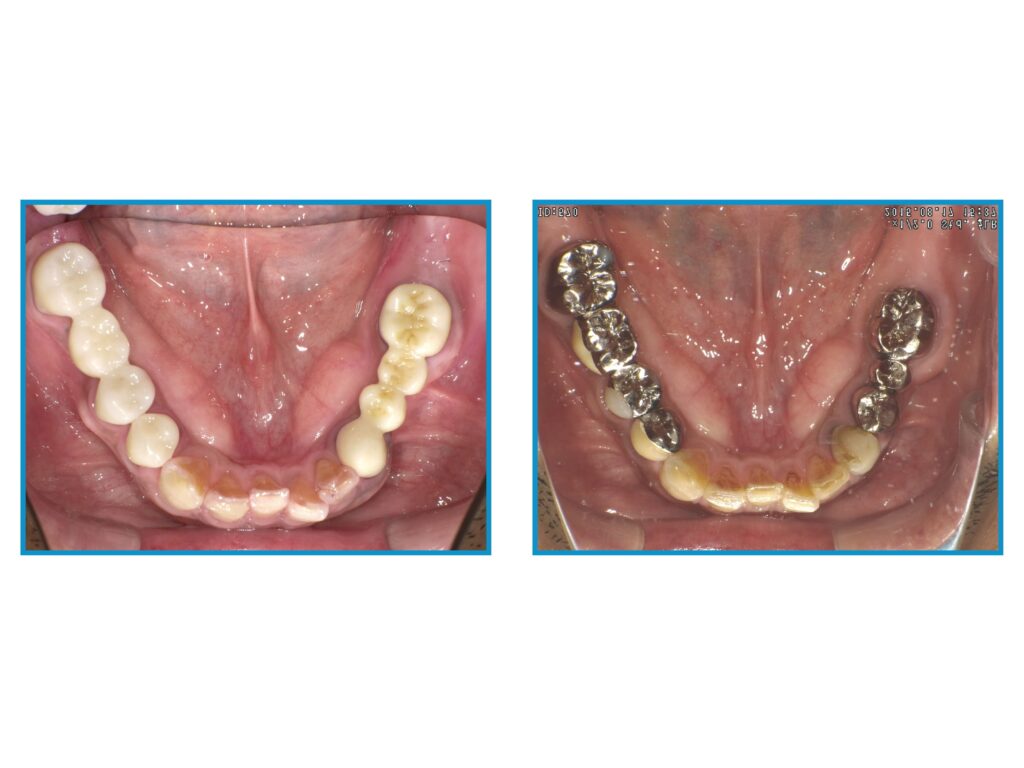

↓メタルフリー治療を受けた患者様